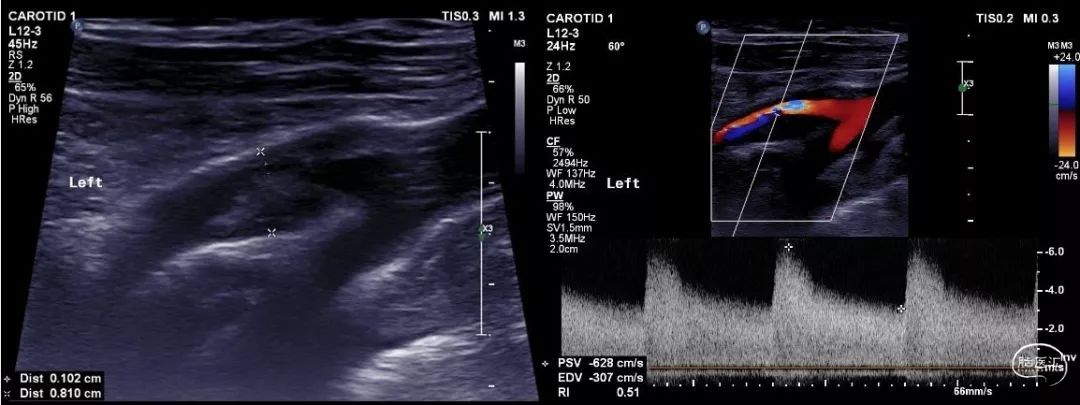

↑↑↑颈动脉超声提示:左侧颈动脉球部前壁、后壁、外侧壁探及27.1×4.4mm低回声为主不均回声环形斑块,残余内径1.0mm,原始内径8.1mm,流速升高达628cm/s,远端流速减低53 cm/s,频谱形态改变,峰时后延。